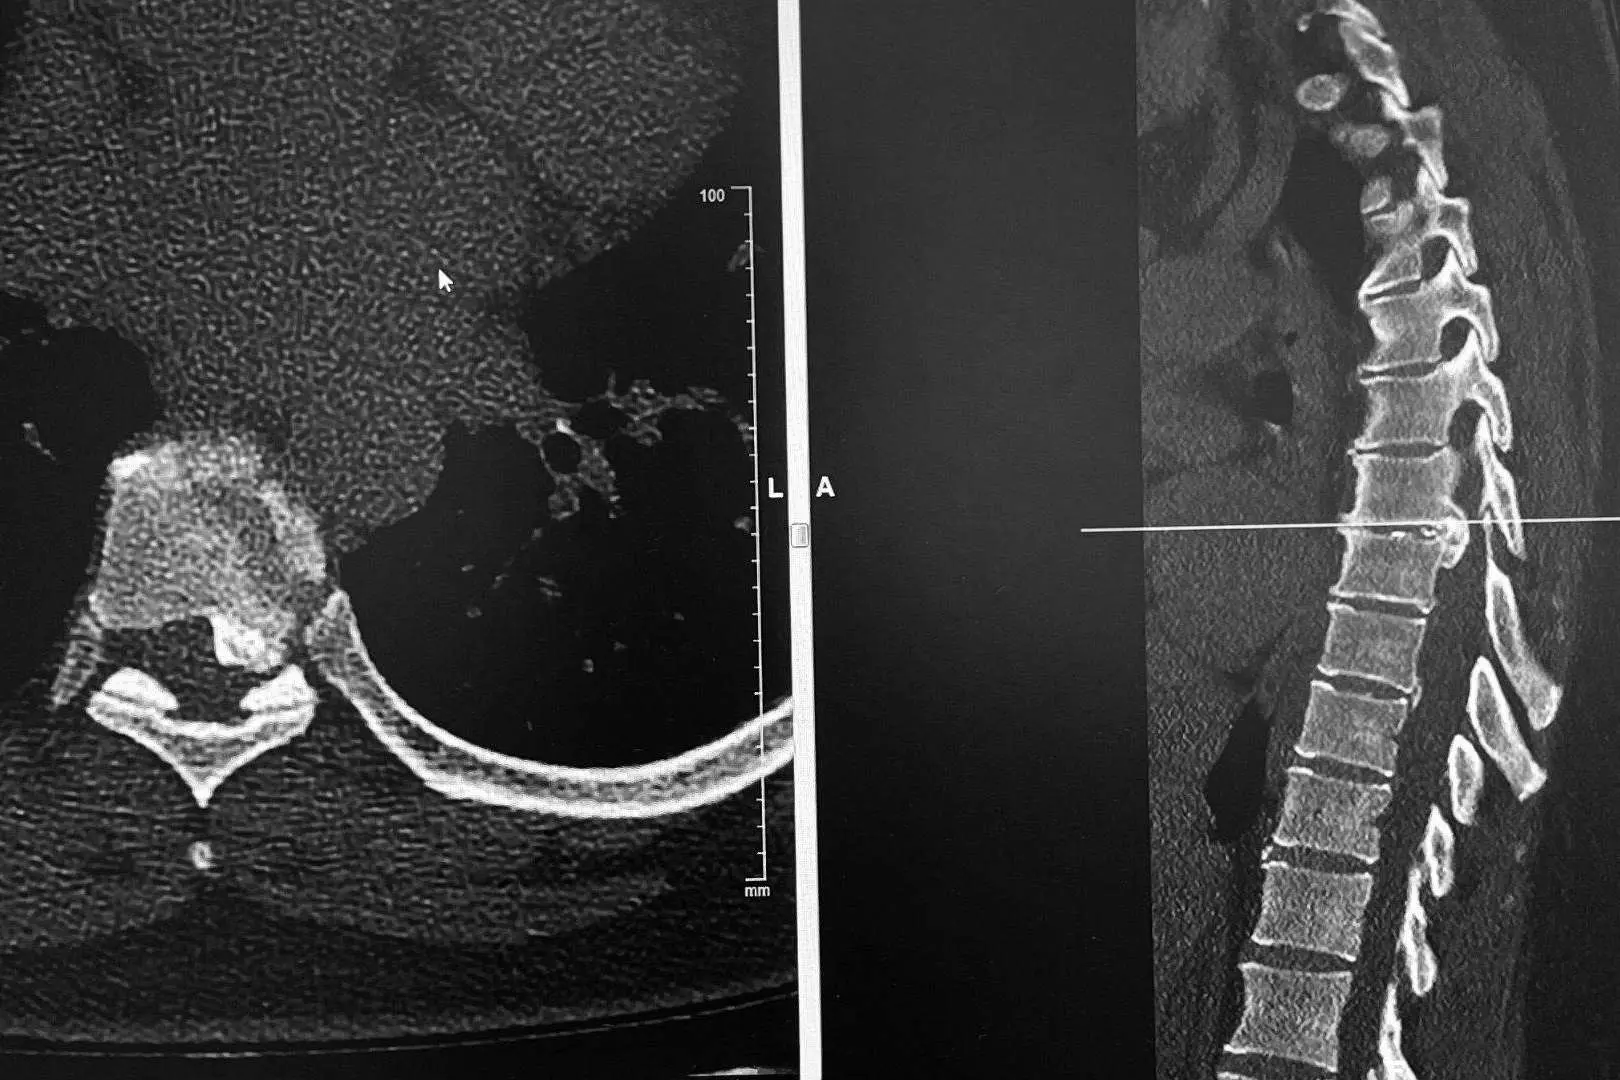

Los discos dorsales son tejidos semejantes a un cojín esponjoso que se encuentran entre las vértebras de la columna. Las hernias aparecen cuando uno de los discos sobresale de entre las vértebras, presionando los nervios y la médula, lo que produce dolor y otros síntomas como la sensación de hormigueo, dependiendo del lugar en el que se originen.

Es común que con la edad, el material gelatinoso que amortigua los discos se debilite y desaparezca, posibilitando movimientos que los desvíe de su posición original, produciendo de esta manera una hernia. Cuando el disco llega a presionar la médula o algún otro nervio importante, es posible que el paciente presente sensación de adormecimiento en las extremidades y, en casos más graves, debilidad en las extremidades o dificultad para el movimiento.

Existen diferentes maneras de detectar una hernia discal, pero en todo caso, es el especialista médico el que debe valorar al paciente y especificar el método de diagnóstico que mejor se adapte a sus necesidades y a la naturaleza de su lesión. El tratamiento dependerá de la gravedad de la hernia. Por regla general, el tratamiento es inicialmente conservador con el uso de medicamentos, reposo, rehabilitación e infiltraciones en su caso.